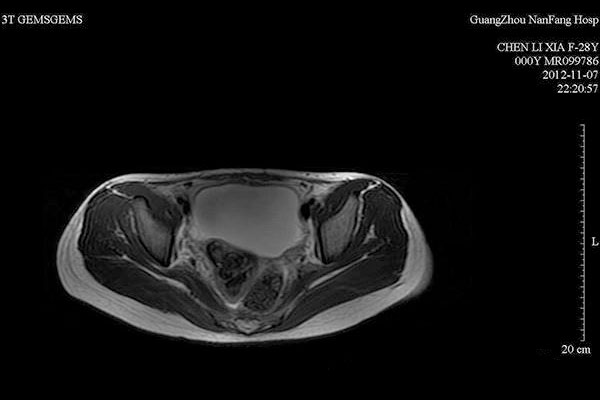

宫腔积液检查结果(示例)

B超检查下的盆腔积液